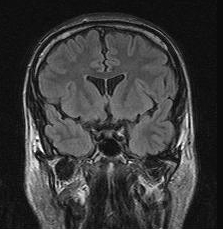

- T1W image: (brain, sagitta slice, arachnid cyst)